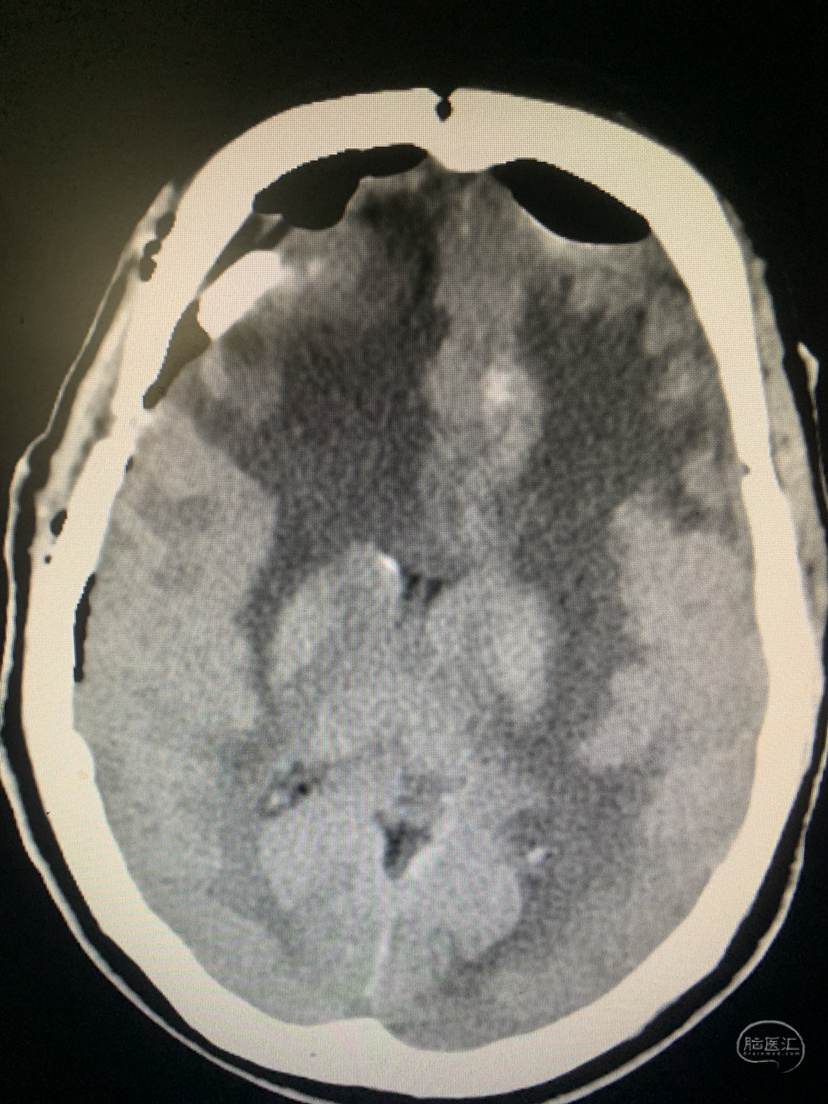

术前术后对比

术后CT

术后16天患者步行出院。